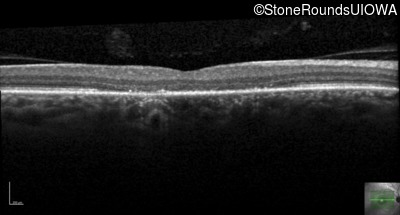

This 44 year old man became photophobic about 6 years ago. He has been taking Imuran since his kidney transplant 23 years ago.

| Senior-Loken Syndrome | NPHP1 | Gly343Arg G(GG)>A(GG) | Deletion of Entire Gene | AR |